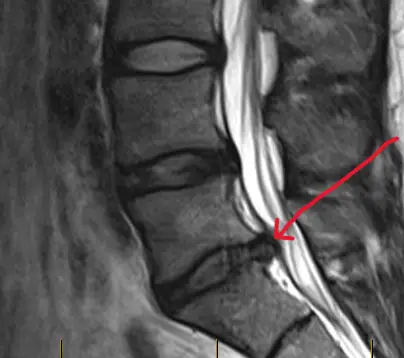

One of the biggest surprises I learned was that pain doesn’t always match up with the severity of the bulging disc. I remember seeing scans of people with much worse looking scans than mine, yet their symptoms weren’t nearly as bad as mine.

The reality is that imaging doesn’t always correlate with pain.

Some people with bulging discs feel little to no pain, while others with similar conditions experience intense discomfort. So, it’s more important to listen to your body and how it feels, rather than just looking at the scan or pain level.